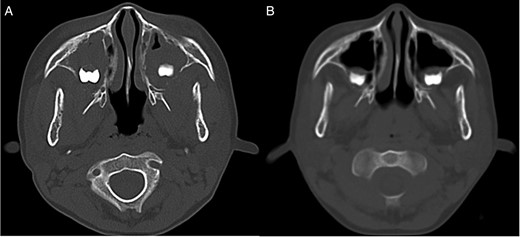

CT image. (A) CT image showing bilateral mass lesions within the maxillary sinuses, with osteolysis involving the posterior walls (right: 3.8 × 3.7 × 2.5 cm, left 3.5 × 3.1 × 2.5 cm). (B) CT image after one course of chemotherapy showing partial reduction of the masses.

The patient underwent chemotherapy based on the Japanese Paediatric Leukaemia/Lymphoma Study Group B-NHL03 protocol [2]. After one course of chemotherapy, CT images showed partial reduction in the size of the masses in the maxillary sinuses (Fig. 1B). Following two courses of chemotherapy, complete remission of abnormal uptake in the entire body was confirmed by PET/CT imaging (Fig. 3B). To date, the patient is alive and under regular surveillance by the Department of Paediatric Haematology and Oncology.